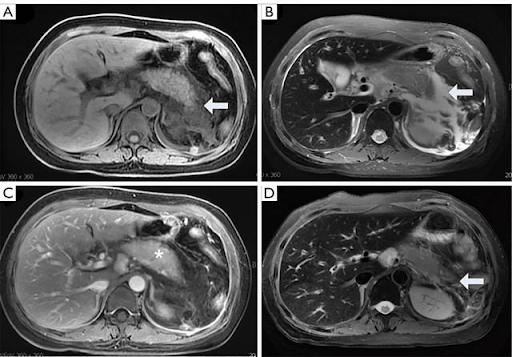

- MRI

- Higher sensitivity in early disease

- Longer to obtain

- Revised Atlanta Criteria

- Six CT morphological features

- Interstitial edema

- Parenchymal enhancement by IV contrast

- Necrotizing findings

- Lack of parenchymal enhancement

- Peripancreatic fluid collection or walled-off necrosis

- Acute peripancreatic fluid collection

- Homogenous fluid collection

- Confined to normal peripancreatic fascial planes

- No definable encapsulating wall

- Adjacent to pancreas (no intrapancreatic extension)

- Pancreatic pseudocyst

- Well-circumscribed, well-defined wall with homogenous fluid density

- No non-liquid component

- Acute necrotic collection

- Heterogenous with non-liquid density of varying degrees

- No definable wall

- Intra-, or extra-pancreatic in location

- Walled-off necrosis

- Heterogenous with liquid and non-liquid densities

- Well-defined wall that is completely encapsulated